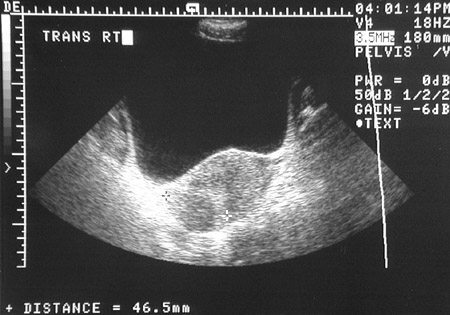

![]() | These pelvic ultrasound views above and below demonstrate a large posterior uterine leiomyoma (marked by the x and + cursors to give the size) measuring 4.6 x 3.9 x 5.0 cm. Note how circumscribed and rounded this tumor mass is. This leiomyoma was large enough to impinge upon the endometrial cavity and cause abnormal bleeding with menometrorrhagia. |